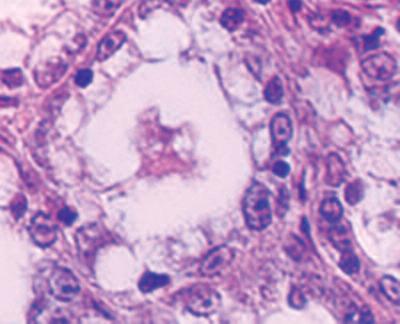

Nella figura A è possibile vedere la struttura del tessuto di un seno non predisposto per l’allattamento, caratterizzato dalla struttura densa di tessuto connettivo che circonda il condotto del latte, al centro dell'immagine, in gran parte chiuso.

In netto contrasto, la figura B mostra la struttura cellulare di un seno predisposto all’allattamento, caratterizzato da tessuto connettivo lasso, la presenza di cellule della ghiandola principale necessaria per la produzione di latte (piccoli cerchi bianchi), nonché il condotto del latte ampiamente aperto (al centro dell'immagine).

A. Condotto del latte (chiuso) nel tessuto del seno in condizioni normali

B. Condotto del latte (aperto) durante l’allattamento

A Ripresa di un condotto del latte al microscopio, sito in un seno non predisposto all’allattamento (chiuso)

B. In funzione dell’allattamento si ristruttura il tessuto mammario. Il condotto è aperto e il latte può uscire.